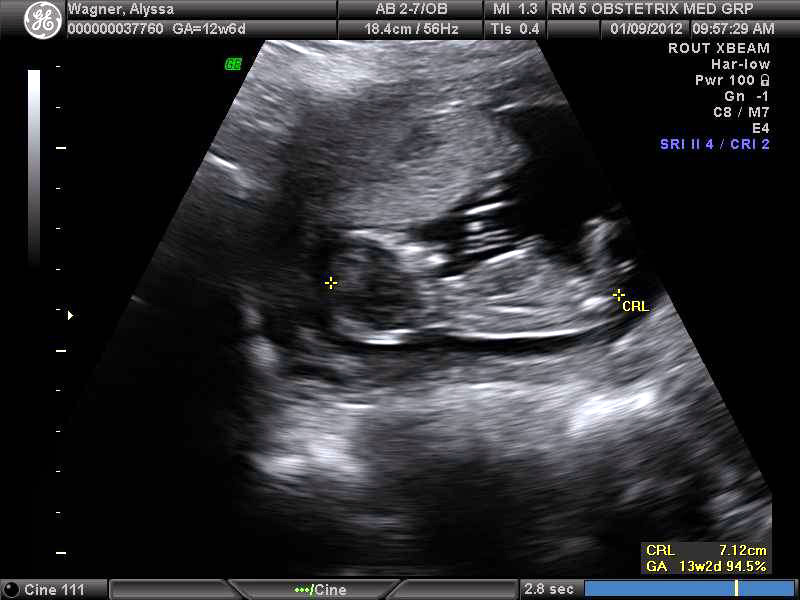

Boy

I think boy also. Second pic has the nub!